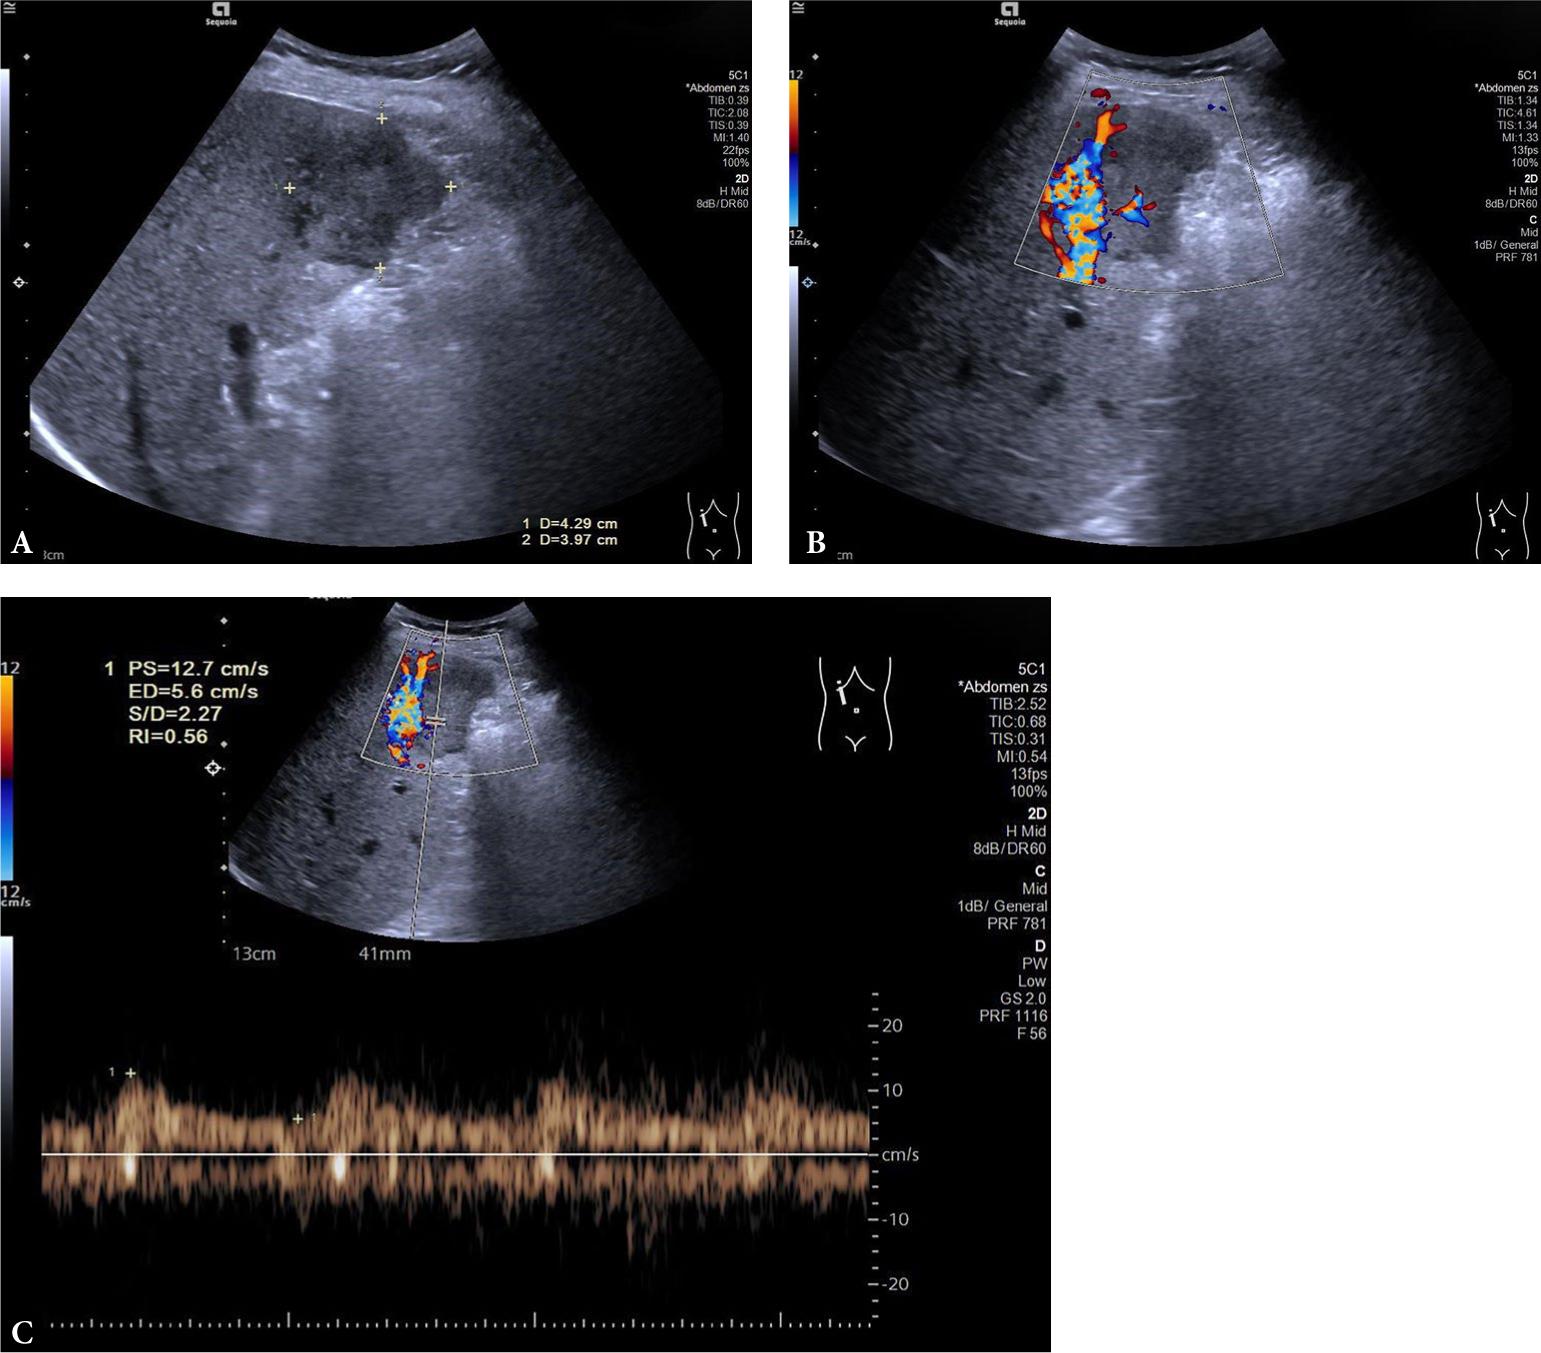

Fig. 3.